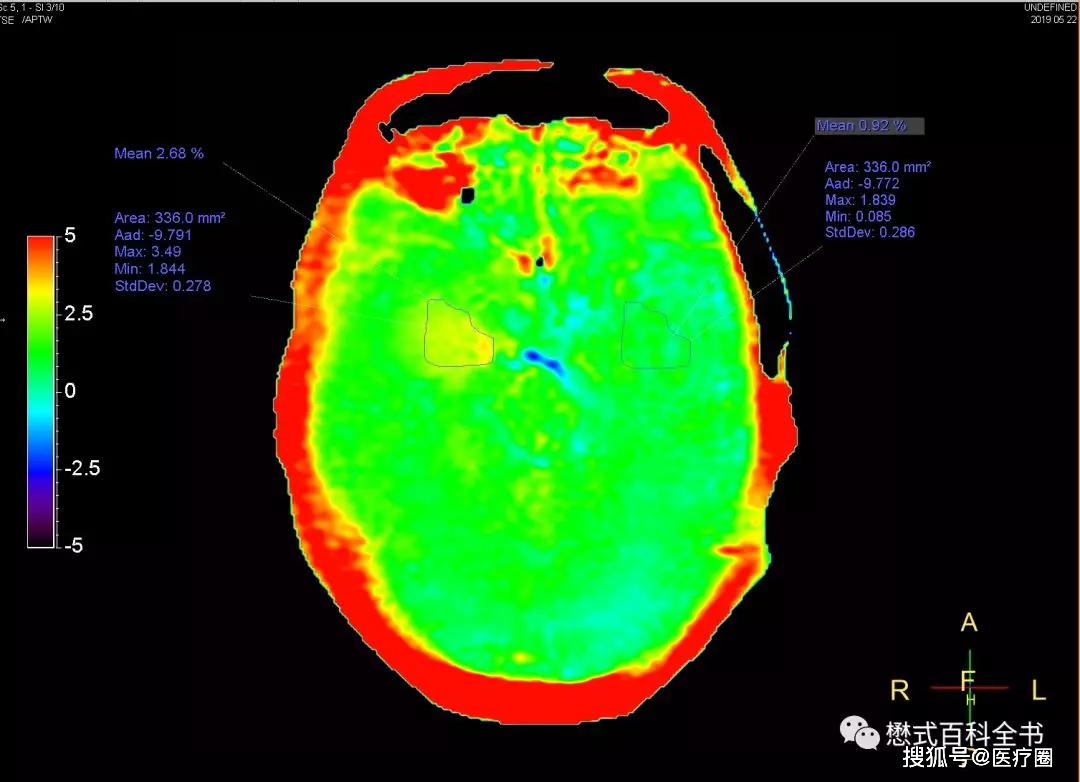

穷人的分子影像学apt

图片尺寸1080x782